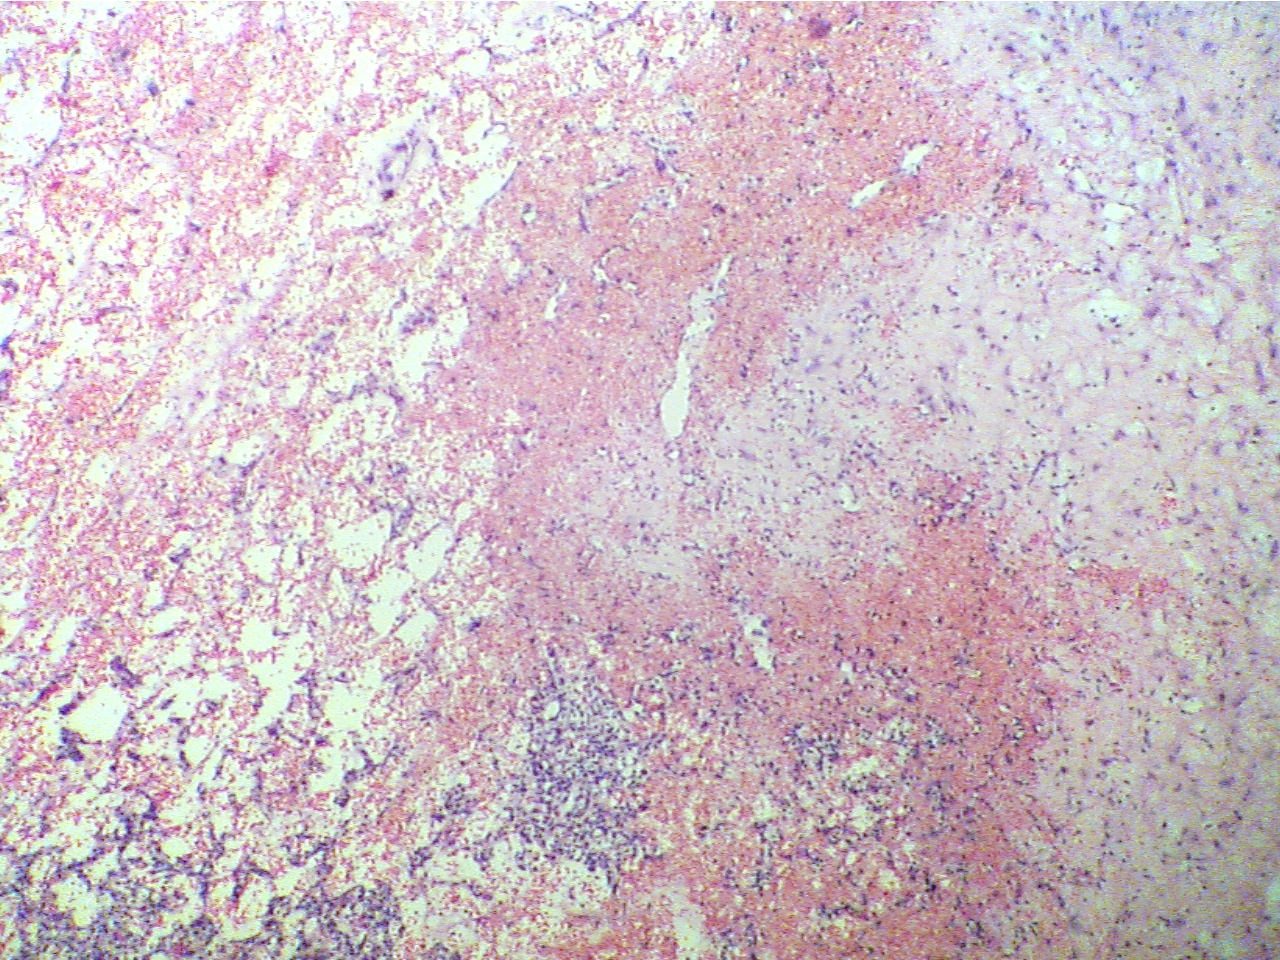

Note that tubular cells have undergone extensive proliferation and have lost

their characteristic appearance. They look more like undifferentiated cells and

there is extensive stroma filled with red blood cells between the cancer cells.

Neoplasia at right, hemorrhaging neoplasia at center and left